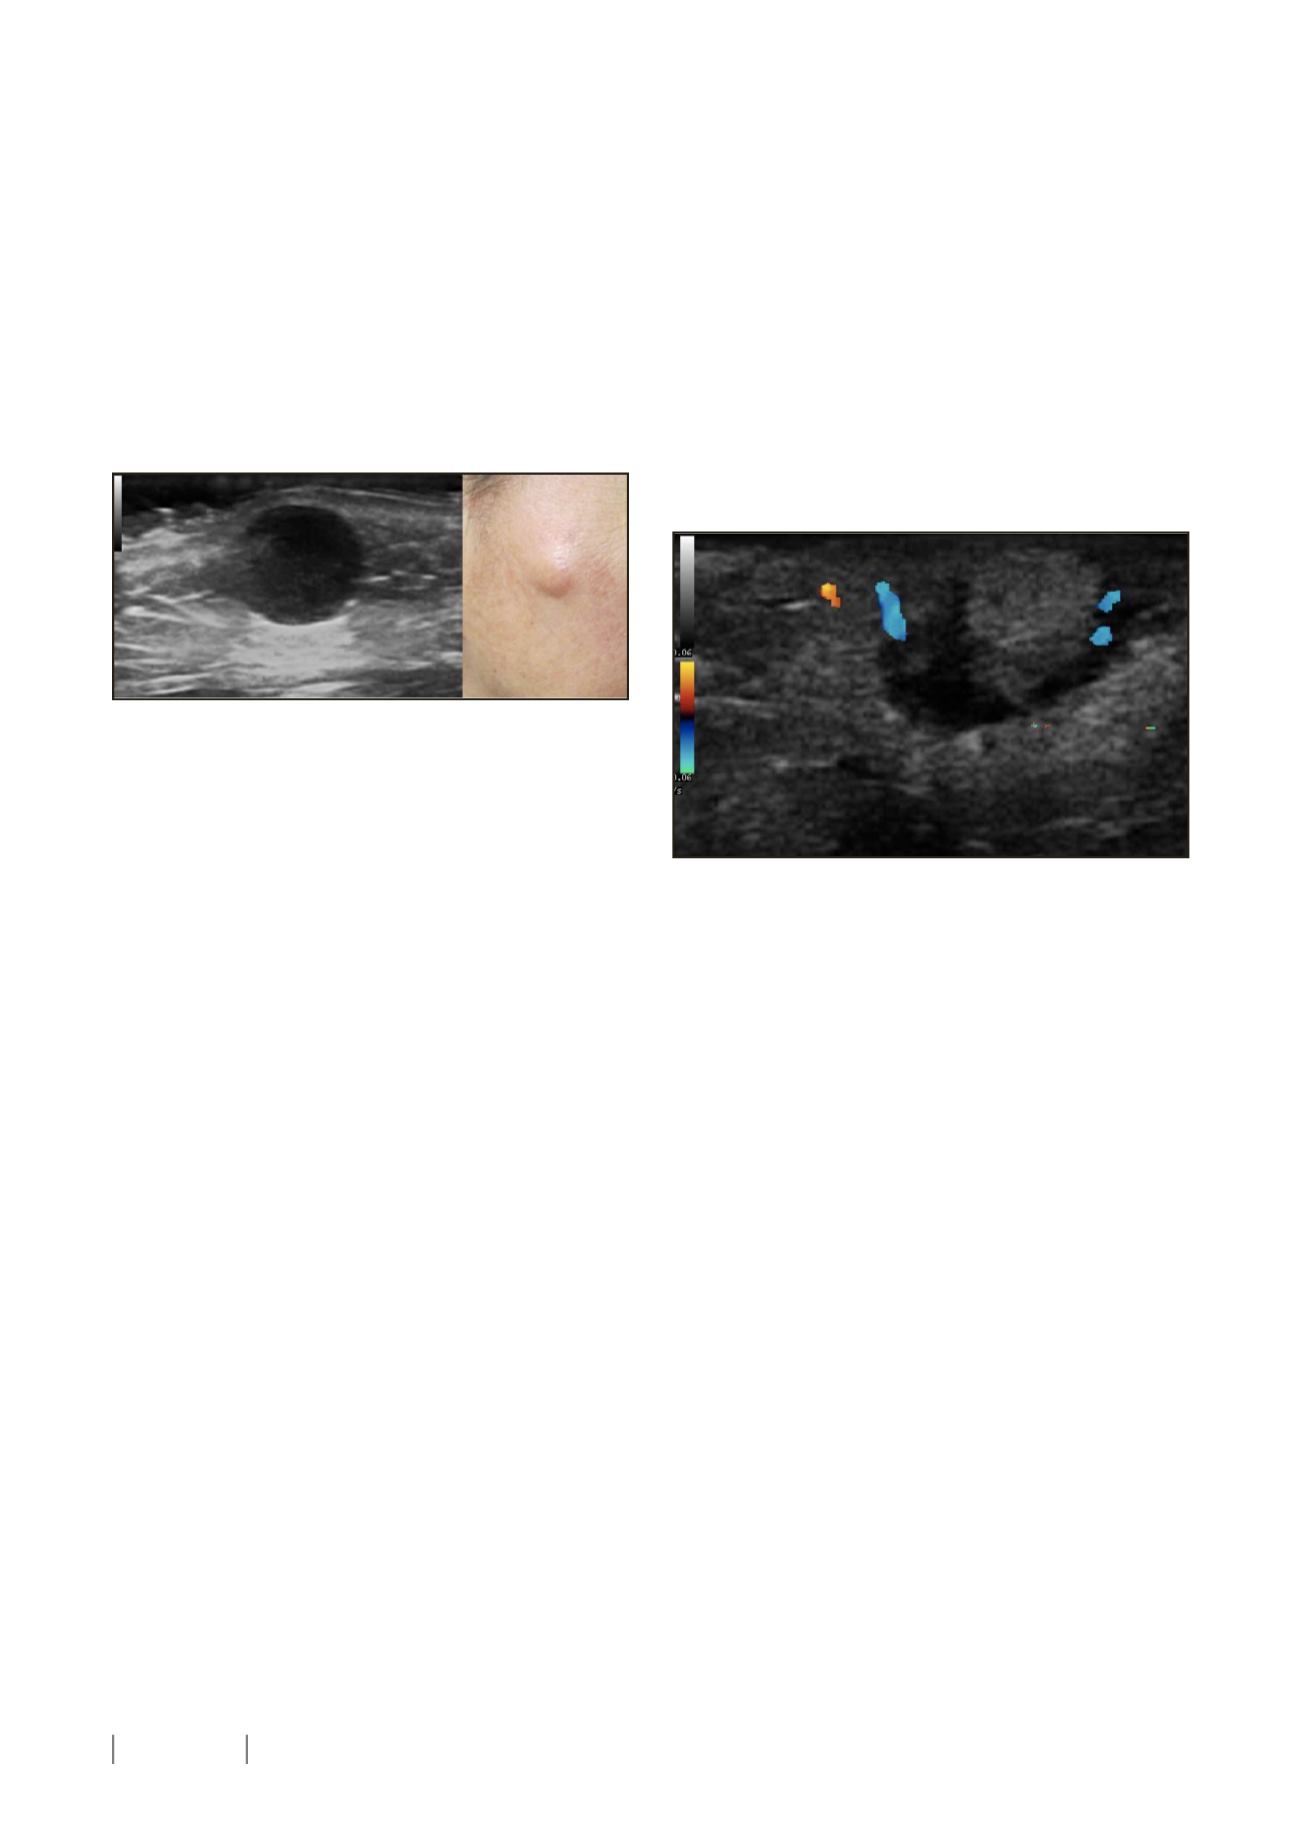

Ecográficamente se caracterizan por presentar una imagen

redondeada, bien definida, anecogénica localizada en la dermis

o tejido celular subcutáneo que puede presentar una conexión

con la epidermis llamada punctum, siendo este el hallazgo más

característico aunque no este presente en todas las exploraciones.

Es frecuente observar algunos artefactos como son el refuerzo

posterior y las sombras acústicas laterales. La exploración con

Doppler color no muestra vascularización en el interior de la

lesión (1,2). (Figura 1)

Figura 1. Quiste epidérmico en mejilla derecha. Imagen redondeada, bien

definida, anecogénica localizada en la unión de la dermis con tejido celular

subcutáneo que muestran un refuerzo posterior intenso y se intuyen

sombras acústicas laterales.